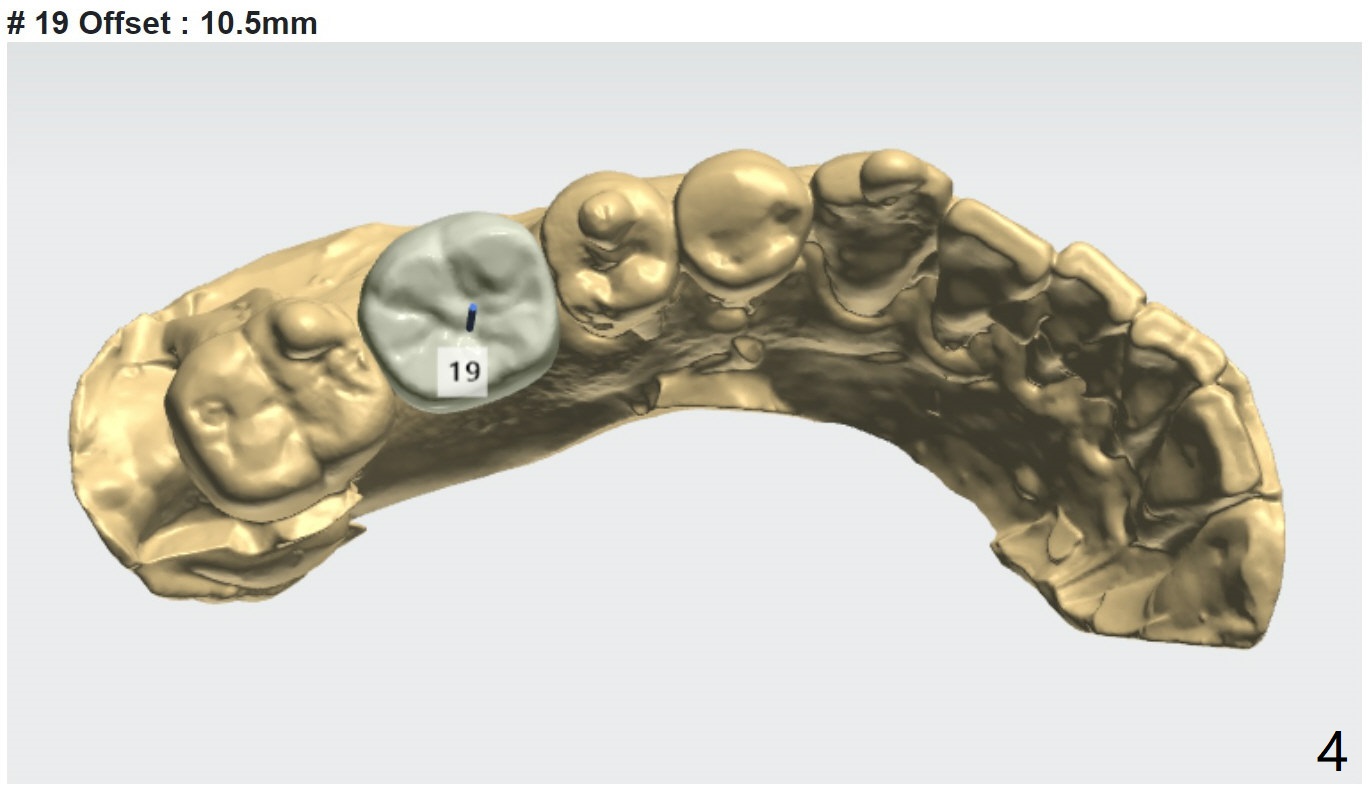

下颌第一磨牙植体长度取决因素

Submandibular Fossa, UF